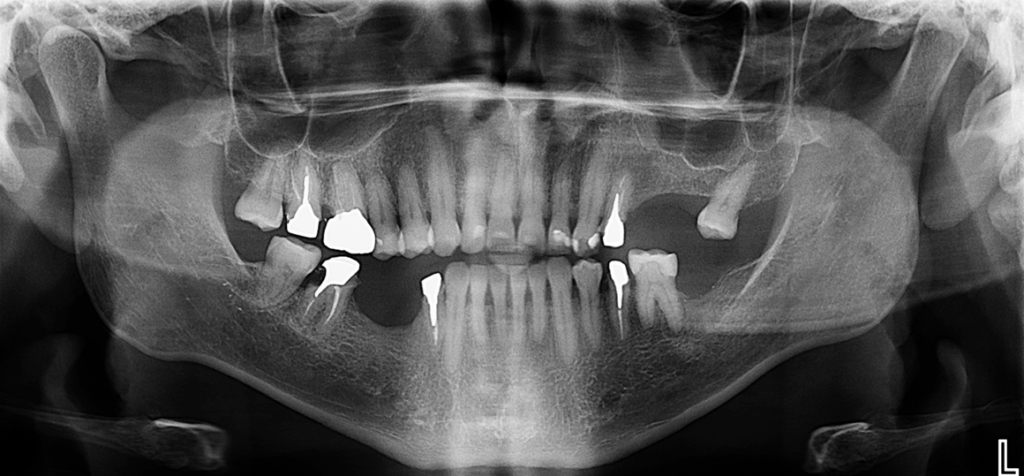

Radiografia Panorámica

En la radiografía panorámica se evidencia múltiples piezas dentarias con material restaurador y protésico, tratamientos de conductos en piezas 17,16,24,35,44,47 y lesión apical en pieza 16.

Si bien las radiografías panorámicas continúan siendo útiles como primera aproximación diagnóstica, presentan limitaciones importantes debido a la superposición de estructuras, la posible distorsión de la imagen o la orientación del foramen, que puede ocultar su presencia. En este caso, los múltiples agujeros mentonianos del lado izquierdo no fueron evidenciados en la radiografía panorámica. La tomografía computarizada de haz cónico permitió identificarlos con precisión, demostrando su valor como herramienta indispensable para el diagnóstico detallado y la planificación quirúrgica, especialmente en la colocación de implantes en esta región (2).